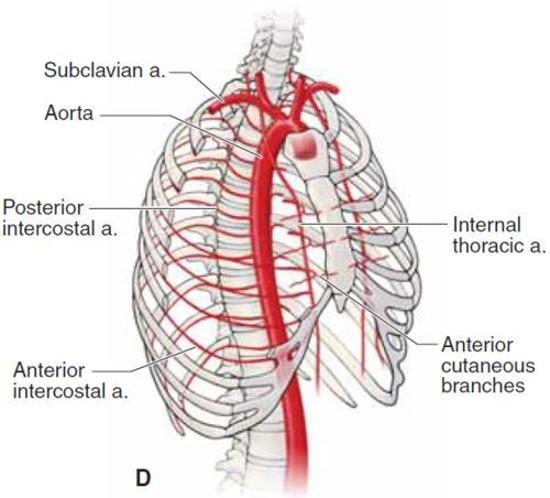

- Blood supply to the rib cage originates from what 2 places?

- what 2 arteries supply the intercostal spaces of the rib cage

- what branch off of the subclavian artery goes down specifically to the diaphragm?

aorta and subclavian artery

Anterior and posterior intercostal arteries

notice how branches from the aorta go around and supply the rib cage

the internal thoracic artery

Anterior intercostal arteries:

- These arteries branch from where?

- then this originates from where?

internal thoracic artery

- Internal thoracic artery originates from subclavian artery

the internal thoracic artery comes from the ____________ vein and then runs behind the anterior ________?

subclavian vein

anterior sternum

notice the internal thoracic artery coming down right near the sternum

The Anterior intercostal arteries supply which intercostal spaces?

- The lower intercostal spaces supplied by what?

1-9

posterior intercostal arteries

notice how the intercostal arteries run superior and inferior in the intercostal spaces

look at all the arteries and their relationship

look at how the posterior intercostal arteries come from the back and wrap around the intercostal spaces from the back